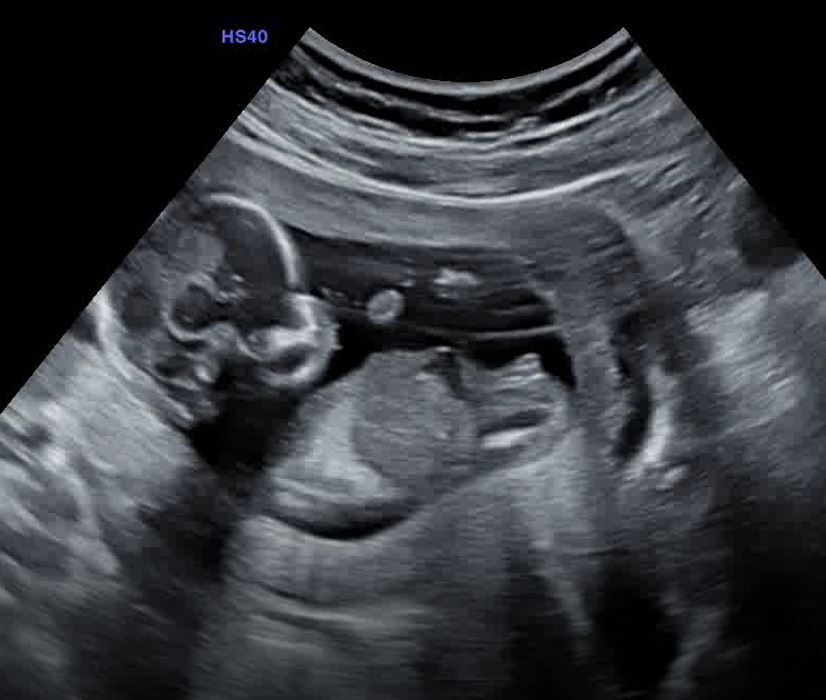

Hello everyone... I got my genderscan today (14 weeks now) but the results weren't convincing for me ... What do you think of it? Boy or girl?

your 12 week looked super girly to me, and this is ALL girl!!!! congratsssss